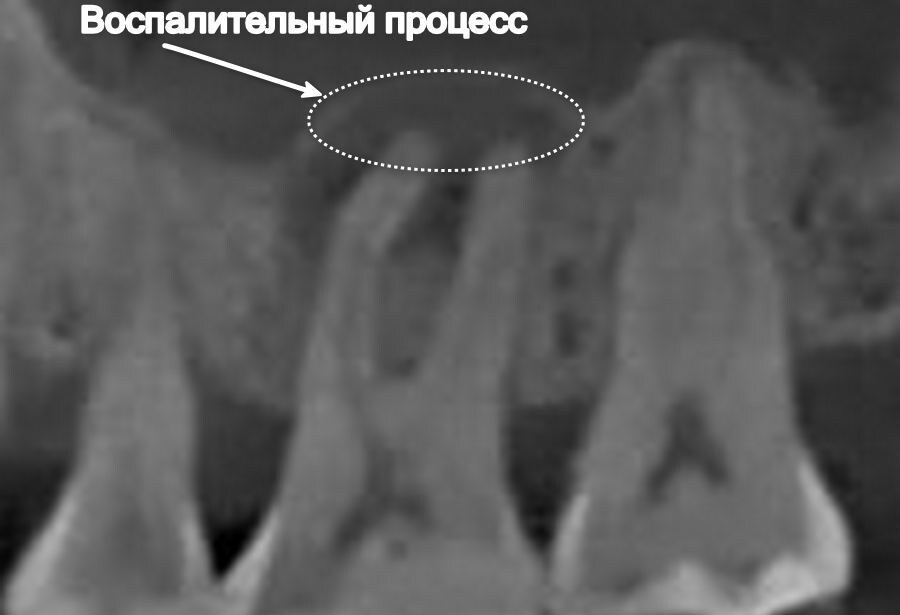

Зуб до лечения

Радикулярная киста зуба 1.6

Яна внимательно относится к здоровью полости рта, поэтому у нее нет проблем с зубами👍 Девушка записалась на прием к стоматологу для планового осмотра перед длительной поездкой в другую страну. Визуально зубы кажутся полностью здоровыми, но чтобы исключить все возможные сценарии, выполняем КТ. Находим радикулярную кисту зуба 1.6😳

Радикулярная киста — это патологическое образование, связанное с корнем зуба, чаще всего возникающее в результате хронического воспаления в области верхушки корня (апикального периодонтита). Это наиболее распространенный вид одонтогенных кист.